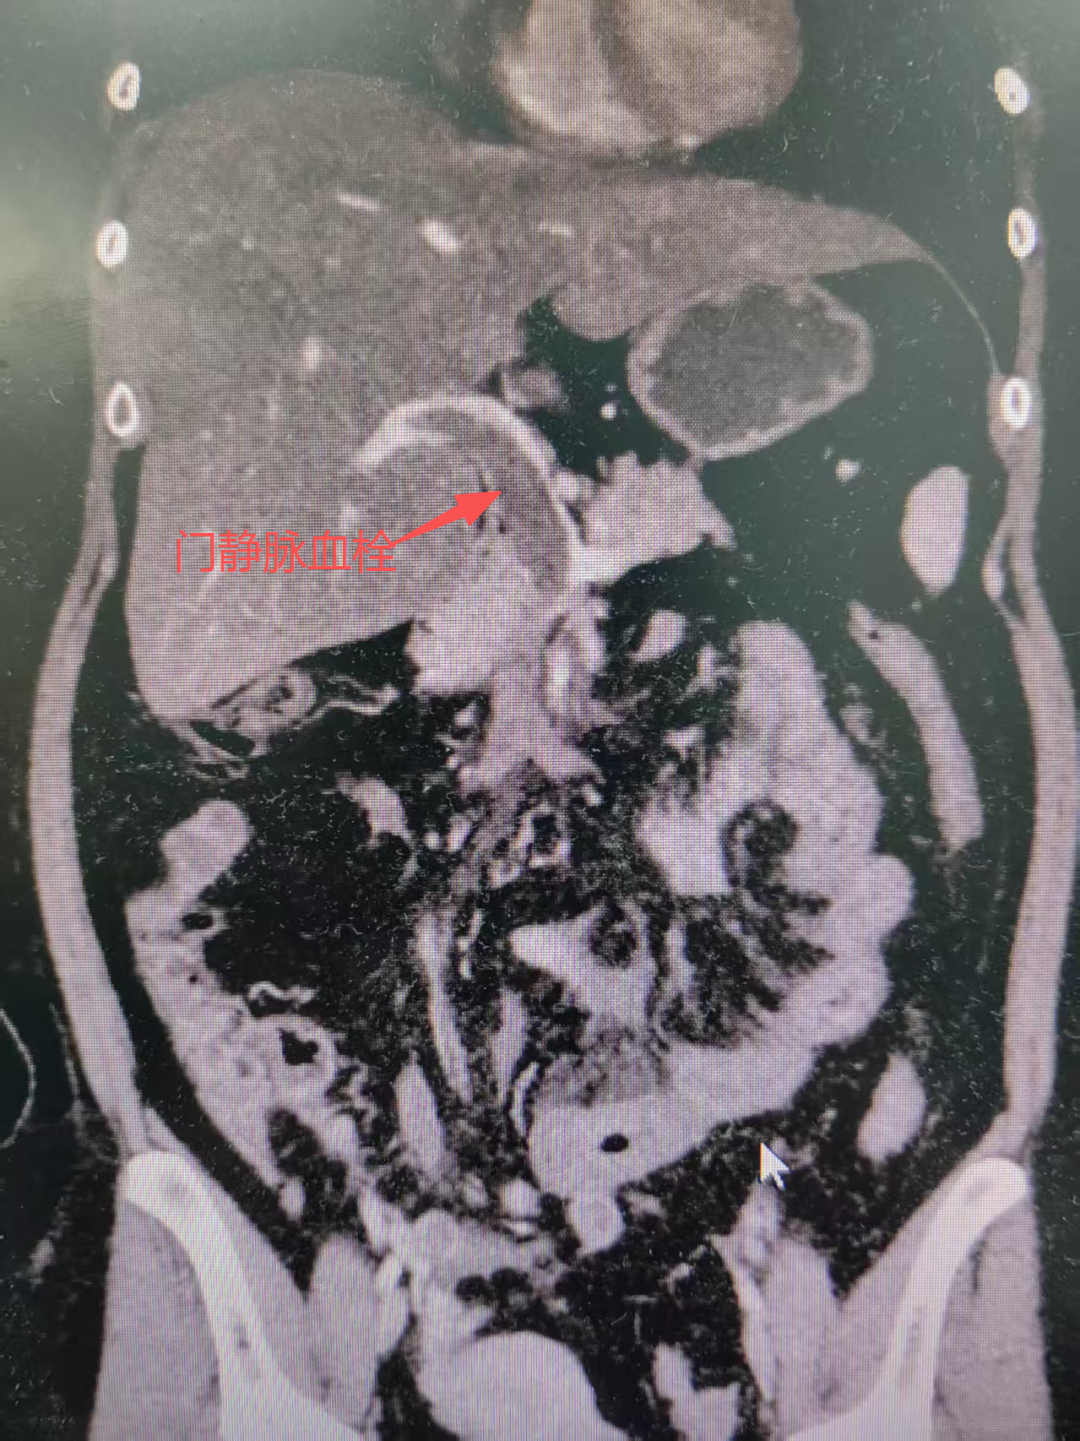

入院后,医疗团队争分夺秒,立即为梁女士完善了全腹部增强CT检查。

结果回报犹如拨开迷雾,真相浮出水面:“门静脉见充盈缺损影,注意血栓形成可能,左中腹部局部肠系膜密度增高,相应小肠壁似水肿。”

至此,隐藏在梁女士腹痛背后的真正“元凶”——门静脉血栓形成被成功锁定!这意味着,血栓已经导致肠道血流严重障碍,随时可能发展为广泛肠坏死、感染性休克,梁女士的生命危在旦夕!